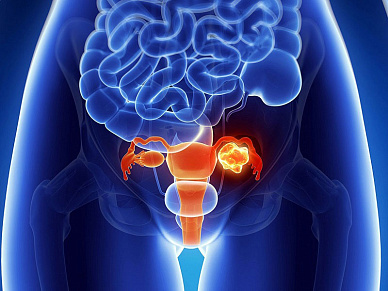

- КТ органов малого таза у женщин с контрастированием